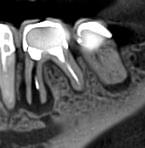

Ми розуміємо, наскільки важлива деталізація в ендодонтії та терапевтичному лікуванні.

Завдяки флагманському обладнанню PLANMECA, ми отримуємо знімки з мінімальним рівнем шумів та

високою роздільною здатністю, що дозволяє чітко візуалізувати морфологію кореневих каналів,

приховані каріозні порожнини та стан періапікальних тканин.